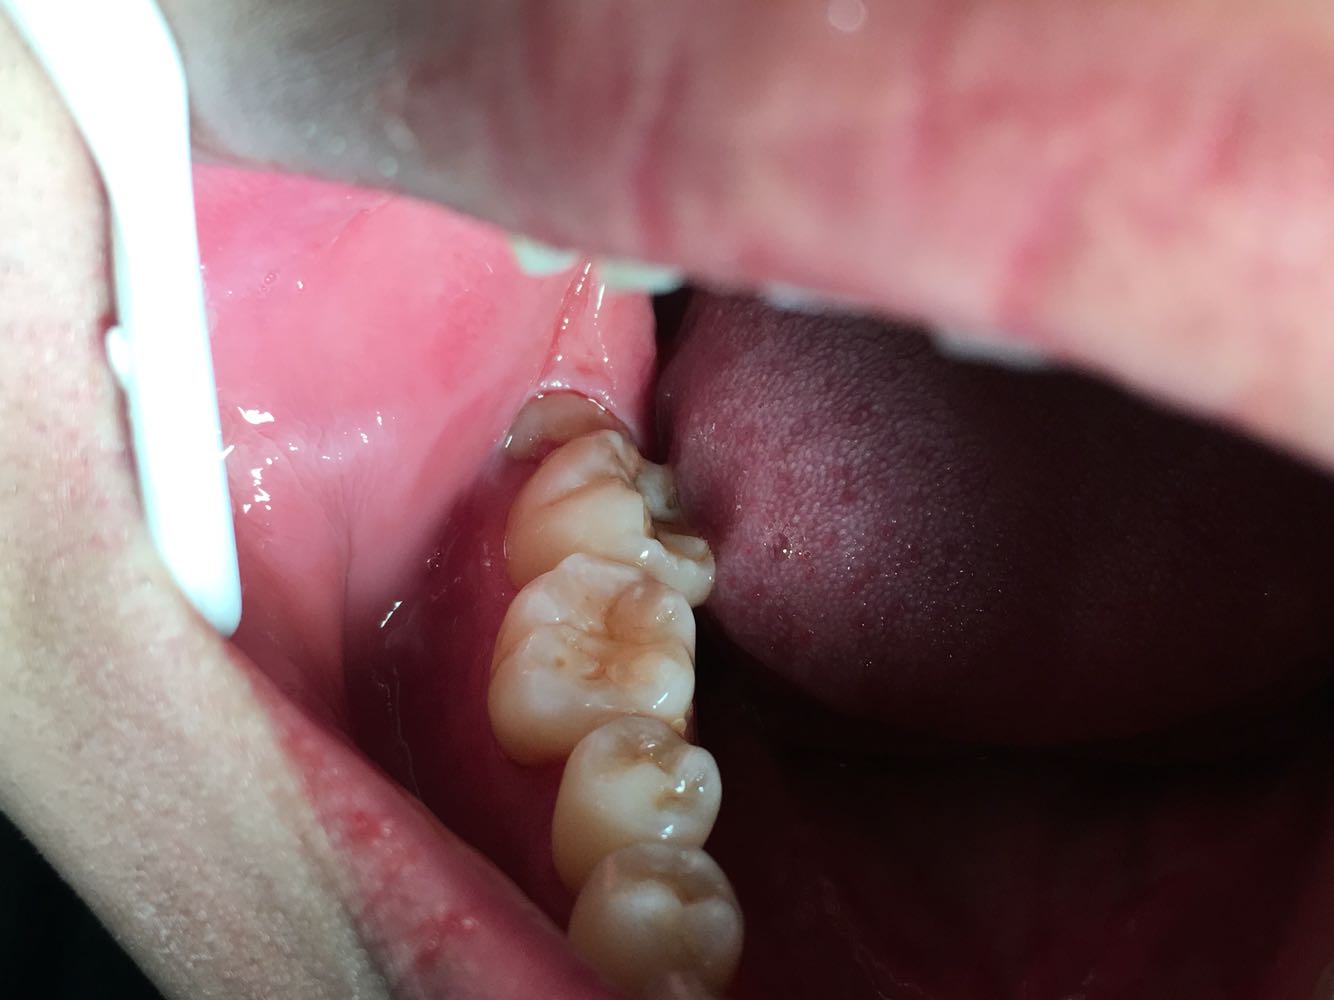

查体 辅查

查体:48牙齿水平阻生,牙龈无红肿,47无松动。 辅查:全景片,38,48牙齿水平阻生